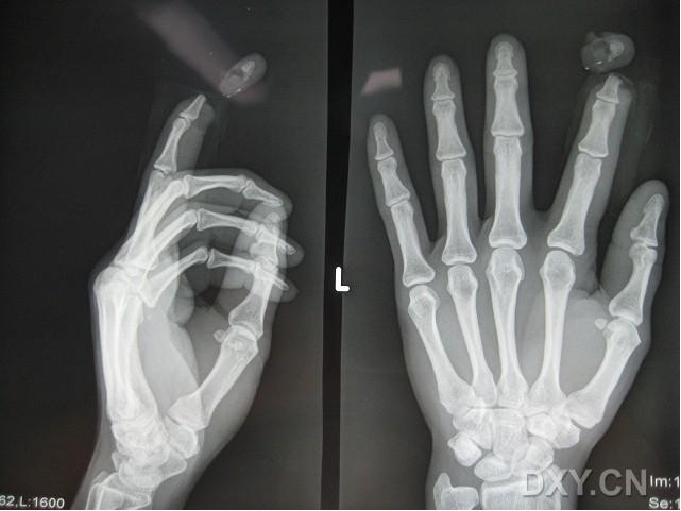

邻指皮瓣

患者,女,音乐老师,25岁,洗衣服时不慎被洗衣机绞伤左示指致左示指指尖离断。